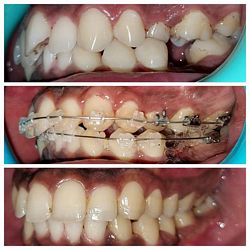

Intra-oral : Pre, Mid & Post-treatment : Right Lateral View